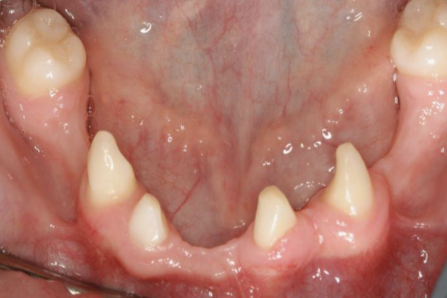

missing 1-5 teeth; ectodermal dysplasia

hypodontia